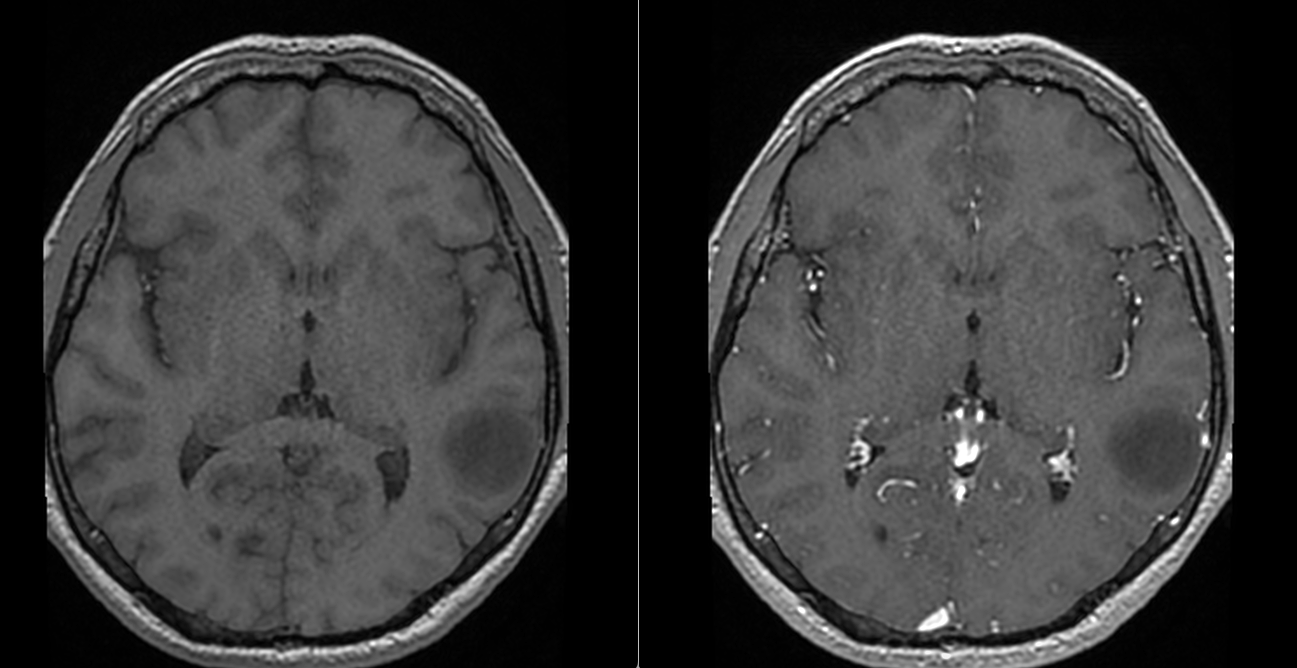

RMN-ul cerebral a evidențiat o tumoră temporală stângă cu semnal hiperintens în secvențele T2 și FLAIR, hiposemnal T1 și fără priză de contrast — un profil imagistic sugestiv pentru un gliom de grad mic.

Spectroscopia RMN a susținut caracterul de proliferare tumorală glială, deși, așa cum se întâmplă frecvent în aceste leziuni, diagnosticul de certitudine nu putea fi stabilit doar imagistic, ci necesita confirmare histopatologică.